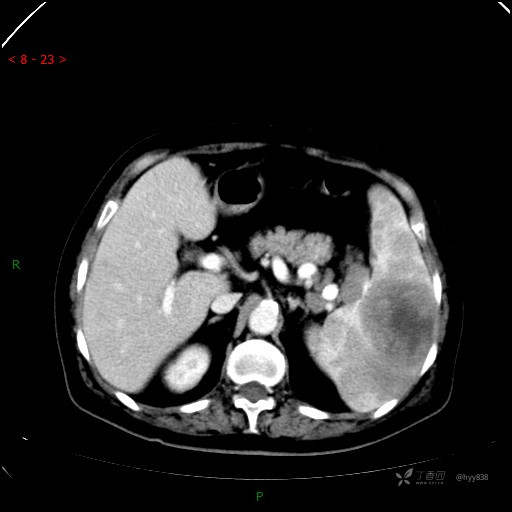

上腹部CT平扫

动脉期